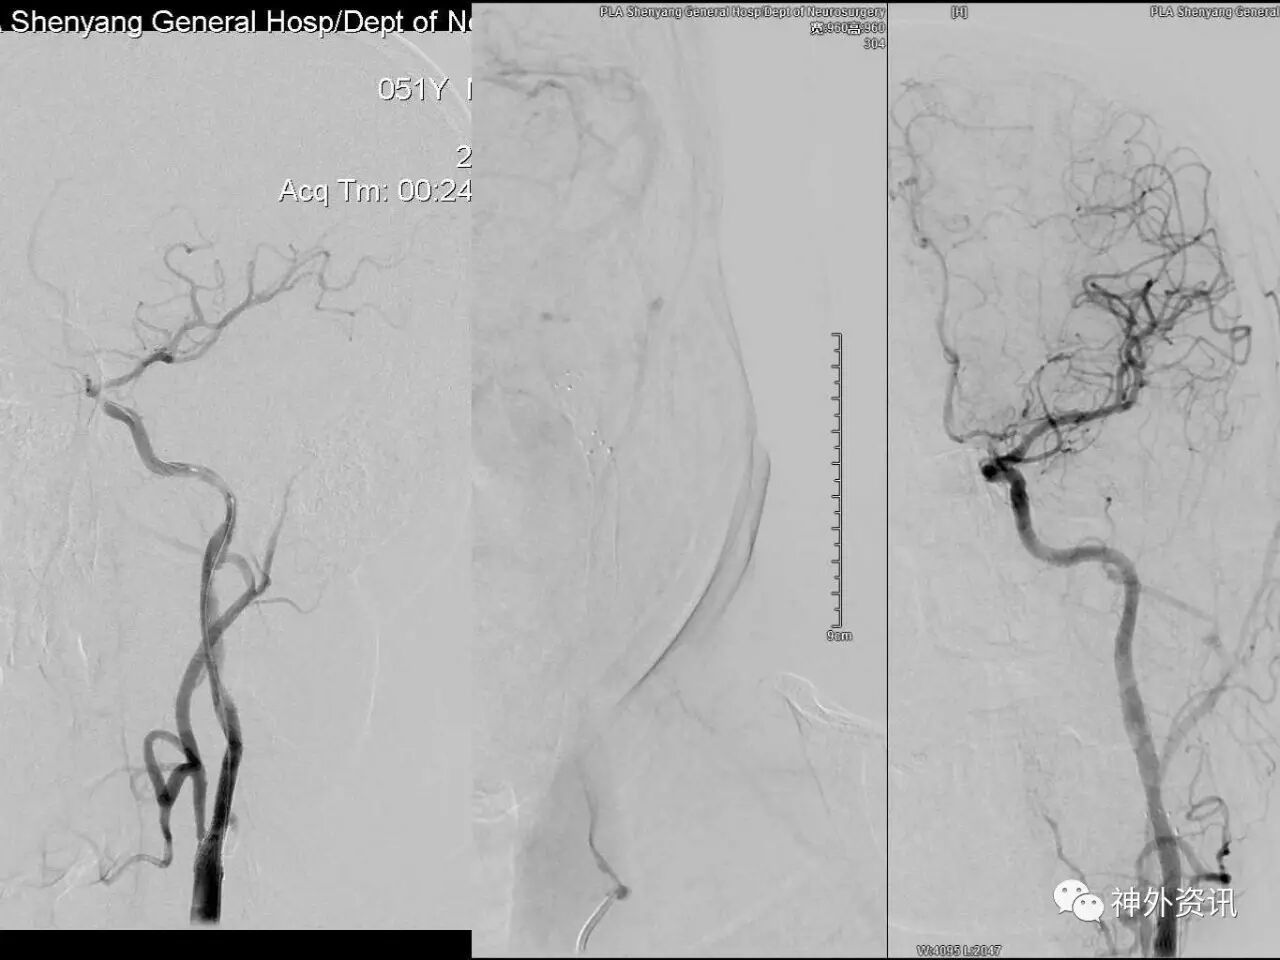

在东北地区率先开展了颈内动脉、大脑中动脉及基底动脉闭塞血管内再通、颅内动脉栓塞急性期取栓、血流导向装置治疗大型宽颈动脉瘤等,对颅内动脉瘤、动静脉畸形、颈动脉及颅内动脉狭窄、颈内动脉海绵窦瘘、硬脑膜动静脉瘘等外科治疗具有较深的造诣。完成脑血管造影8600余例,各类脑血管病介入手术共4500余例,动脉瘤、动静脉畸形、脑肿瘤、脑出血及脑外伤等外科手术1500余例。